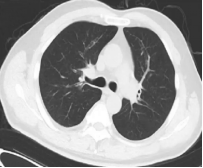

胸部CT:可见气道壁增厚、管腔轻度狭窄、气道壁少量渗出,存在中心性支气管扩张征象及双肺散在磨玻璃样浸润影。